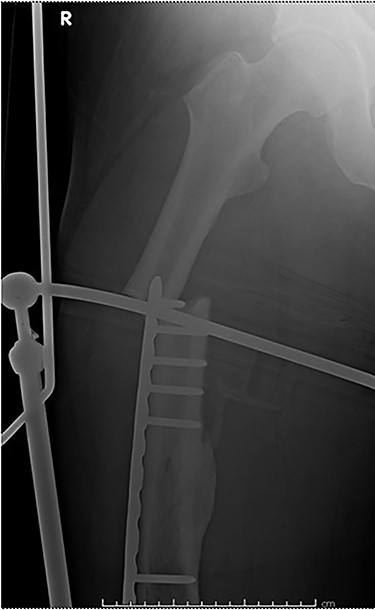

Case 4 (Figs 8–10): once again, screw placement too close to the fracture site has resulted in internal plate stresses exceeding its load-bearing capacity.

Inter-fragmentary screws have been utilized here. This lady may have benefited from placing an anterior bridging plate at the time of her original procedure if it was not possible to avoid this screw configuration.